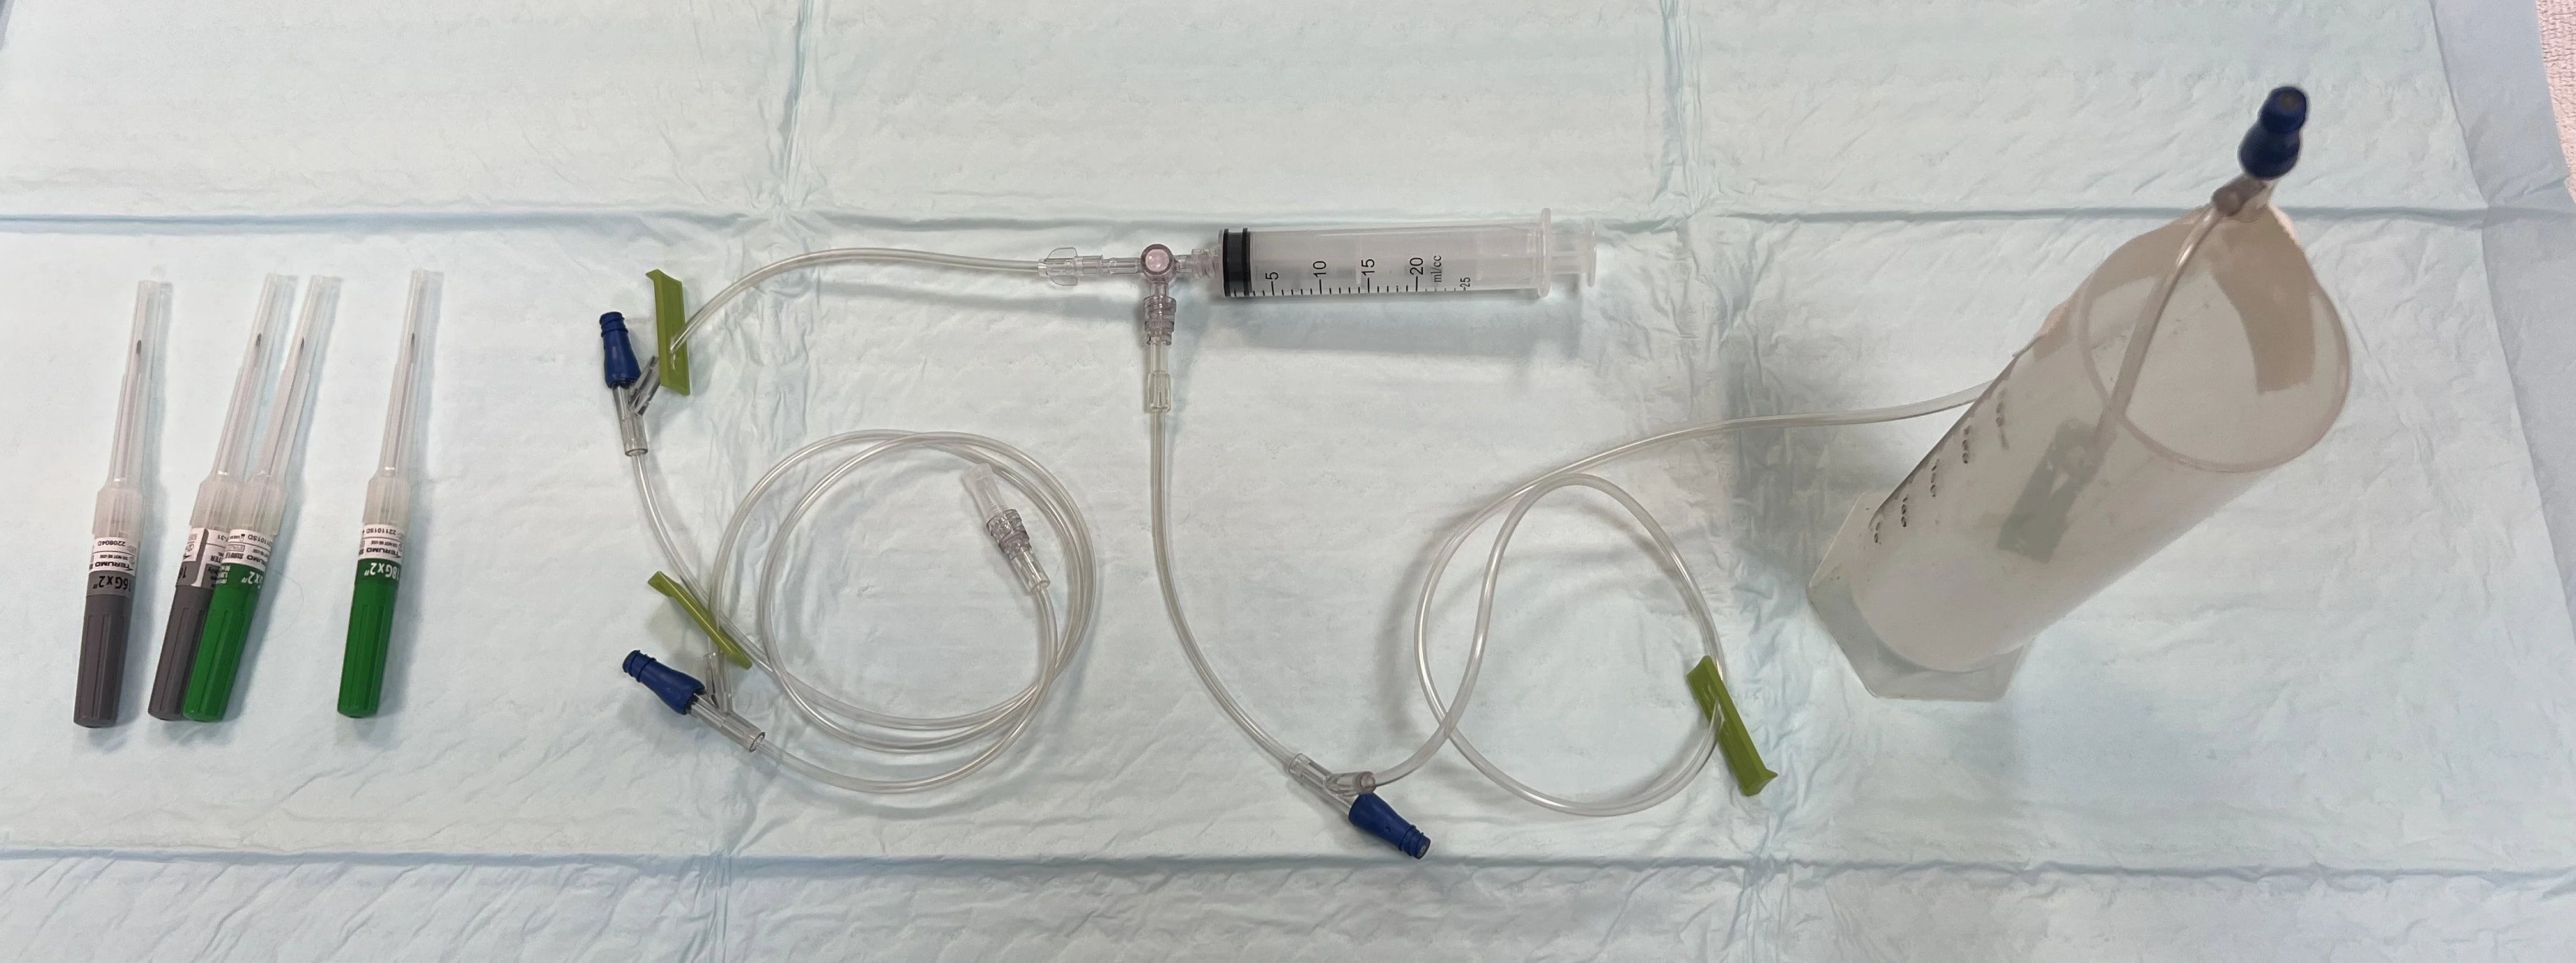

Hypodermic needle (cats, 22 gauge, 1 inch; dogs, 18-22 gauge, 1-1.5 inch based on patient size), over-the-needle catheter (cats, 22 gauge; dogs, 18-22 gauge), or butterfly catheter (cats or small dogs, 23 gauge)

2 extension sets

3-way stopcock

Collection container

Syringes (6-60 mL based on amount and viscosity of fluid expected, size of needle/catheter, and operator preference)

Step 1: Prepare Collection Equipment

Using sterile technique, connect the 3-way stopcock to a syringe and 2 extension sets, with one set connected to the needle and the other taped inside the collection container. Ensure the stopcock is turned off to the patient.